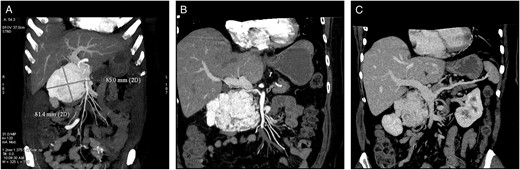

A 53-year-old, obese (body mass index 30.9 kg m−2), Caucasian woman was referred to our department with non-specific abdominal discomfort as the only presenting symptom. A large hypervascularized mass in the area of the pancreatic head was shown on abdominal ultrasonography and computed tomography (CT). There was neither lymphadenopathy nor distant spread found during pre-operative staging. Pre-operative imaging revealed an extremely hypervacularized tumour with abundant collateral vessels from the superior mesenteric artery (SMA), replaced right hepatic artery (HA), gastroduodenal artery (GDA) and right renal artery (RRA), with an early venous filling of the dilated superior mesenteric vein (SMV) and portal vein (PV) (Fig. 1A–C and Fig. 2A and B). The replaced right HA arising from SMA was crossing in between the dilated PV and overfilled tumour-draining veins (Fig. 1B). Abundant venous drainage was found. Extreme dilation of SMV and PV in both extra- and intra-hepatic course could be expected as numerous AV shunts within the tumour were present, but surprisingly, only a non-dilated, gracile splenic vein was found and no spleen enlargement was present (Fig. 1C). For better evaluation of vascular anatomy, selective digital substraction angiography (DSA) was performed. The upper portion of the tumour received main inflow via GDA and replaced right HA, the lower part via several branches of SMA (Fig. 3A and B). Capsular branch of RRA complemented tumour inflow (Fig. 3C).

Cross-sectional CT imaging. (A) Hypervascularized tumour with early venous filling in the arterial phase of CT. (B) Variant subtle right hepatic artery originating from SMA, passing between the dilated PV and draining veins of a paraganglioma. (C) Isolated dilation of the PV with surprisingly gracile splenic vein without any spleen enlargement.